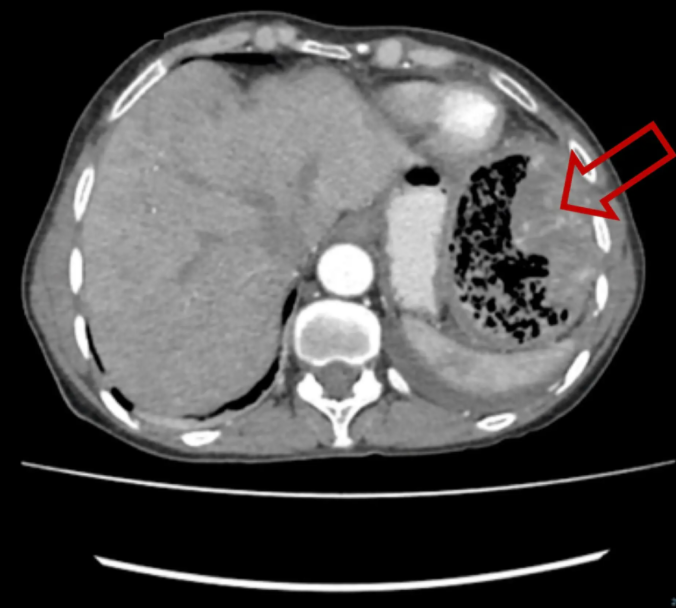

这名患者对突然出现的症状感到惊恐,于是赶紧去看医生。超声波扫描显示她的腹部有一大块纱布。医生们认为,这个黏糊糊的东西应该是在20多年前的手术中留在她的结肠里的。

为什么医院的纱布不卖纱布在身体里20多年!女子突然发烧、腹痛、掉秤 医院一查让人咋舌_https://www.jmylbn.com_新闻资讯_第6张

幸运的是,纱布没有在很难搞的地方,外科医生给她做了一个小手术,将这团纱布取了出来(上图)。

据图片显示,这团纱布看起来很硬,呈棕色,就像古代木乃伊的包裹。